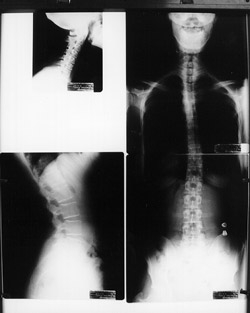

Spinal X-rays may be taken depending on your age, and situation. There are many reasons why we would not take x-rays on certain patients including pregnancy, most children, recent usable spinal x-rays and some other various situations. Aside from these situations, x-rays are a common part of the examination process when looking for vertebral subluxations. X-rays give us important information including the position of the spinal bones, and the quality of the spine and safety of adjusting it. X-rays also tell us the relative length of time subluxations may have been involved in your spine. Commonly, most patients receive three spinal x-rays at the beginning of care.

With this important information we can make a more accurate determination of the type of adjustments your spine needs as well as the ongoing frequency of your care. Your x-rays will be explained to you and covered in detail at your Report of Findings. You will be scheduled for your Report of Findings within a few days of your initial visit. This visit is your most important visit and may take up to one hour. It is at your Report of Findings that we will give you a care plan and go over any special instructions you will need to obtain the best and fastest possible results. We have set aside specific times for these visits so as not to interfere with regular patient care hours. Our staff will schedule your Report of Findings with you after your first visit.